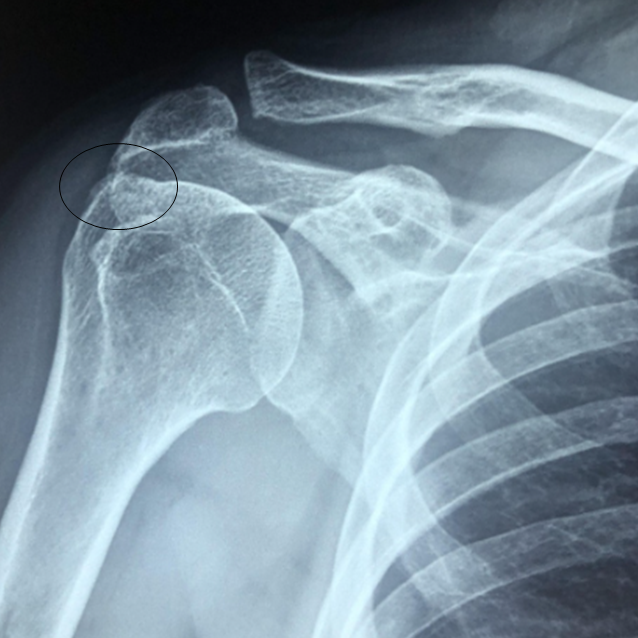

x-ray상 원위부의 돌출 및 불규칙등이 관찰됨.